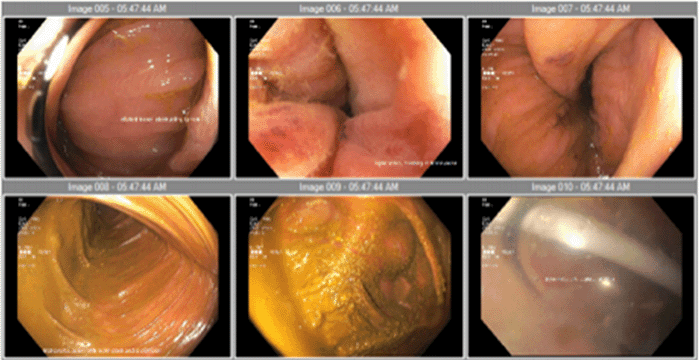

Figure 2. Colonoscopy on Admission. Published with Permission

Grossly distended colon with colonic looping is demonstrated; however, a clear transition point diagnostic of volvulus is absent

The patient presented with three days of abdominal pain and distention with nausea. He denied any past medical or surgical history. He experienced similar painful episodes over the preceding year that resolved spontaneously within 48 hours. On exam, his abdomen was distended with mild tenderness; rectal exam was normal. CT scan showed a distended esophagus, decompressed small bowel, dilated large bowel, and a significantly medialized liver (Figure 1). As the entire colon was enlarged, colonoscopy was performed to rule out an anatomic cause for large bowel obstruction at the rectosigmoid junction. The patient was found to have a grossly distended colon without obstructing lesions or clear transition point consistent with volvulus. Proximal to the sigmoid colon, there were multiple redundant colonic loops that impeded navigation but were ultimately traversed with difficulty (Figure 2). A rectal decompression tube was placed. Given the nondefinitive findings of the colonoscopy, symptomatic improvement of the patient with decompression, and the patient's young age, additional diagnostic workup was performed for a presumed motility disorder. A full thickness excisional rectal biopsy was obtained for evaluation of Hirschsprung disease.